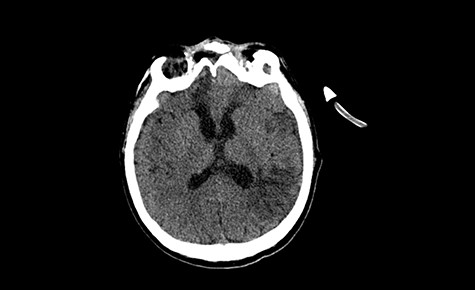

Head CT after polypectomy—seen defects of the upper left orbital wall. (Department of Neurosurgery own material).

In described case, a head CT scan after polypectomy confirmed the subarachnoid hemorrhage (Fig. 1). In addition, the presence of air in the ventricular system was visible, and presence of defects of the upper left orbital wall and ethmoid on both sides (Fig. 3). In the CT scan sphenoid sinus, frontal and ethmoidal sinuses on both sides and right maxillary sinus airless, filled with blood and soft tissue. The changes also concerned the lateral part of the left maxillary sinus (Fig. 4).

The present bone defects were most probably caused by the development of osteomalytic foci as a consequence of the spread of the inflammatory process within the diploe of flat skeletal skull bones, in the course of chronic rhinosinusitis. Both underestimating the severity of complaints in the course of chronic rhinosinusitis and delaying the implementation of surgical treatment led to massive bone destruction, which had an impact on the development of further complications after polypectomy (including subarachnoid hemorrhage). Performed angio-CT excluded any malformations and the probable cause of subarachnoid hemorrhage due to rupture of the aneurysm. Considering the radiological picture and the condition of the patient, it can be concluded that the persistent inflammatory process within sinuses led to dehsomination and subsequent bleeding into the subarachnoid space through discontinuity in the bone structure of the sinuses and orbits.